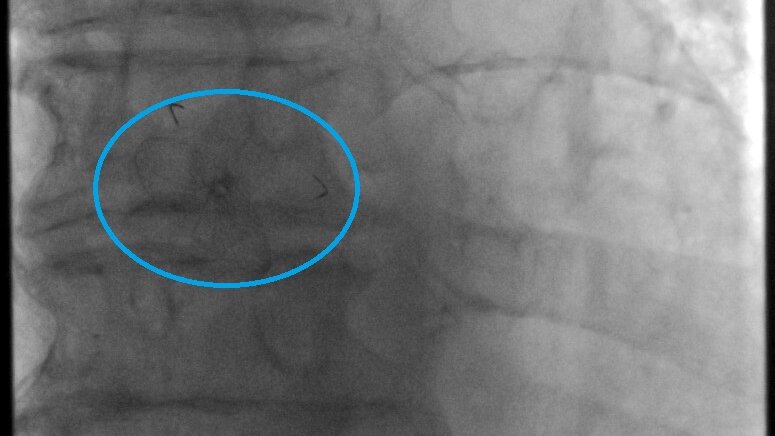

Mit einem rund 30-minütigen minimal-invasiven kardiologischen Eingriff ist es möglich, dieses Loch bei schlagendem Herzen zu schließen. „Der Operateur bringt bei diesem Eingriff einen Katheter über die Leistenvene durch das zu verschließende PFO in den linken Herzvorhof des Patienten. Im Gegensatz zu einer klassischen Herz-OP muss in diesem Fall nicht der Brustkorb geöffnet werden“, so Chefarzt Fürnau.